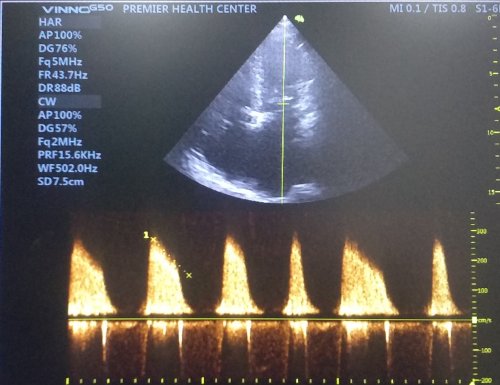

The most common mechanism proposed for palpitation is hyperactive anterior mitral leaflet

Mitral stenosis patients can feel their loud first heat sound (S 1) or varying S1 during atrial fibrillation as palpitation; Mitral valve prolapse with redundant , hyper kinetic motion is probably most common cause of benign palpitation.